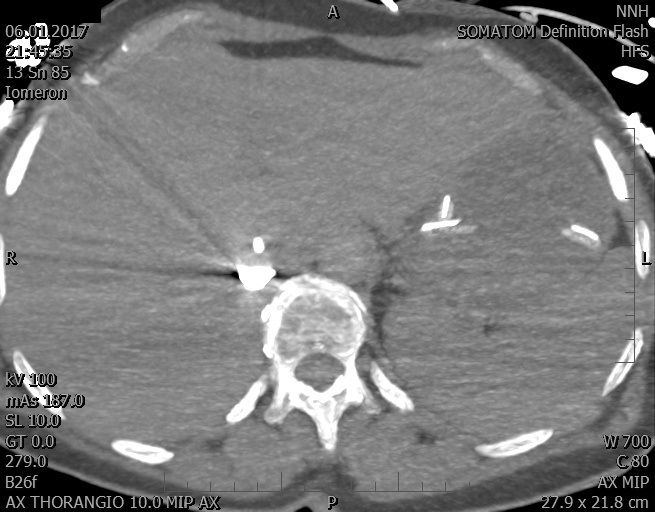

Video 2 - Echokardiograficky byla zjištěna těžká dysfunkce dilatační levé komory s nezvětšenou pravou komorou.Pro nejasnou příčinu zástavy jsme provedli i vyšetření výpočetní tomografií (CT), které vyloučilo plicní embolizaci (série 1 - soubory na konci článku). V den přijetí při přetrvávající oběhové nestabilitě byla nemocná opakovaně defibrilována pro fibrilaci komor se stabilizací rytmu po podání amiodaronu a mesocainu. Dle hemodynamických měření se jednalo o těžký kombinovaný šok. Vstupní laboratorní vyšetření bylo bez větších pozoruhodností. Posléze jsme doplnili anamnézu od příbuzných a zjistili, že pacientka užila do dvou hodin před srdeční zástavou první tabletu amoxicilinu na lehký respirační infekt. Při nevýtěžnosti vstupních vyšetření a nových anamnestických informacích jsme doplnili 14 hodin po kolapsu vyšetření koncentrace tryptázy v séru, která byla extrémně zvýšena (tabulka 2), což nás vedlo k podezření na anafylaxi.